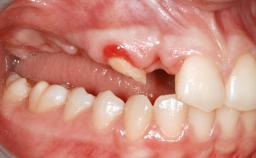

An 80-year-old female patient was referred to clinic for rehabilitation of her dentition. The patient’s medical history revealed no significant findings that would preclude routine dental and oral surgical procedures. She reported no drug allergies and was currently taking no prescription medications.

Her chief complaint was her inability to masticate efficiently due to the recent loss of her mandibular second premolars and first molars bilaterally. She expressed a desire for fixed prostheses in the shortest possible time due to her advanced age, requesting that replacement teeth should look as natural as possible. She was otherwise comfortable and not experiencing any symptoms from her teeth.

Case Type Short Space

Jaw Mandible

Area Posterior